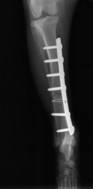

Chirurgia, ortopedia

Wykonujemy szereg zabiegów operacyjnych z zakresu chirurgii miękkiej, jak i twardej. Przeprowadzane przez nas operacje często ratują życie, a niejednokrotnie również polepszają jego jakość.

W przeciwieństwie do wielu gabinetów nasz zespół operuje w składzie 3-osobowym. Jest to niezmiernie ważne, ponieważ ułatwia chirurgowi pracę oraz znacznie skraca czas wykonywania operacji. Dla pacjenta jest to wyznacznikiem profesjonalnie i bezpiecznie wykonanego zabiegu.

Zapewniamy stały nadzór anestezjologiczny i monitoring pacjenta podczas zabiegu oraz opiekę pooperacyjną.

W ramach chirurgii twardej przeprowadzamy m.in. takie zabiegi jak:

• operacyjne leczenie złamań i zwichnięć